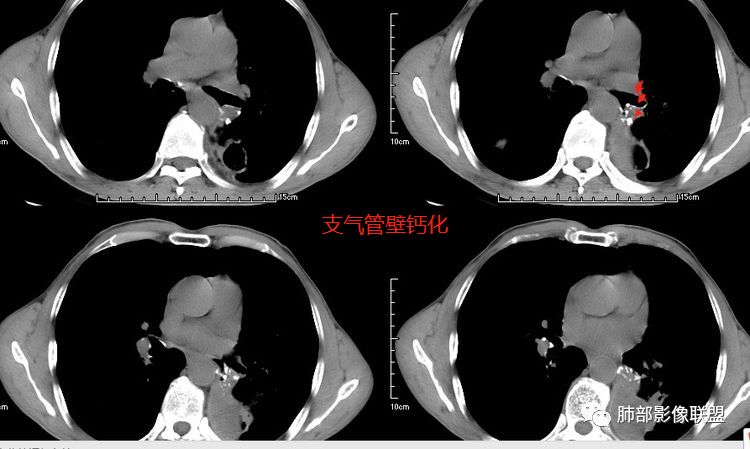

【每日晨读】“洞”灼其“奸”--双肺空洞性转移瘤

患者老年男性,咳嗽、咳痰、痰中带血伴胸闷2月余。长期大量吸烟史。查肝肾功能、血糖、血脂、心肌酶、电解质、血沉、C反应蛋白、抗“O”、类风湿因子、抗核抗体谱无明显异常。肿瘤标志物提示NSE、CYFRA21-1稍升高。胸部CT:肺气肿背景,左肺下叶后基底段不规则肿块影,见支气管截断,内见大片状低密度区及部分血管影,增强轻度强化,远端空洞形成。双肺多发不规则实性结节影、见毛刺、胸膜牵拉及血管集束,结节内见空洞形成,部分可见血管影,多位于胸膜下。双肺见多发肺大泡。综合考虑左下肺恶性病变并双肺转移。鳞癌或淋巴瘤可能。鉴别血管炎性病变及真菌感染。

张延军:双肺多发结节,空洞影,后者洞壁厚薄不均匀,部分腔内丝丝落落,呈分叶征,边缘见毛刺影,病灶大部分位于胸膜下,与血管相连,右肺下叶前基底段结节近段支气管截断,远端见空腔。左肺下叶病灶密度不均,背段支气管壁增厚,管腔狭窄。考虑1.双肺下叶占位性病变伴肺内空洞性转移 2.多原发的占位 3.肉芽肿性血管炎代排。

本病例左肺下叶肿块,有深分叶、毛刺、胸膜牵拉凹陷、支气管截断及纵隔内淋巴结肿大等征象,都均支持病灶为恶性,如腺癌,而且叶间裂的多发结节也提示是腺癌来源可能大;双肺多发结节、肿块,大部分病灶有分叶、毛刺及胸膜凹陷的恶性征象,与原发肿瘤本身的性质有关,所以应该与左肺下叶肿块同源,而且双肺多发病灶内空洞也具有多样性;

此病例中空洞形态多样,内壁不光整,有分隔影,周围未见明显卫星灶及钙化灶,结核不太符合;患者病史慢性病史,无明显发热,缺乏中毒临床表现,急性感染基本排除;各种中性粒细胞胞浆抗体阴性,没有鼻窦炎,肾脏等病史,基本排除血管炎;霉菌性空洞常见于免疫机能低下者, 常为空洞、肺炎、伴“ 晕圈”征的结节及支气管扩张合并存在。